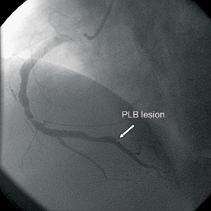

Due to the perfusion finding, a meticulous second look at the PLB territory was performed and a thrombus at the PLB was found. The patient underwent invasive coronary angiography with the lesion area in the mid-RCA stented. Figure 5 shows the focal lesion in the PLB from the invasive coronary angiography.